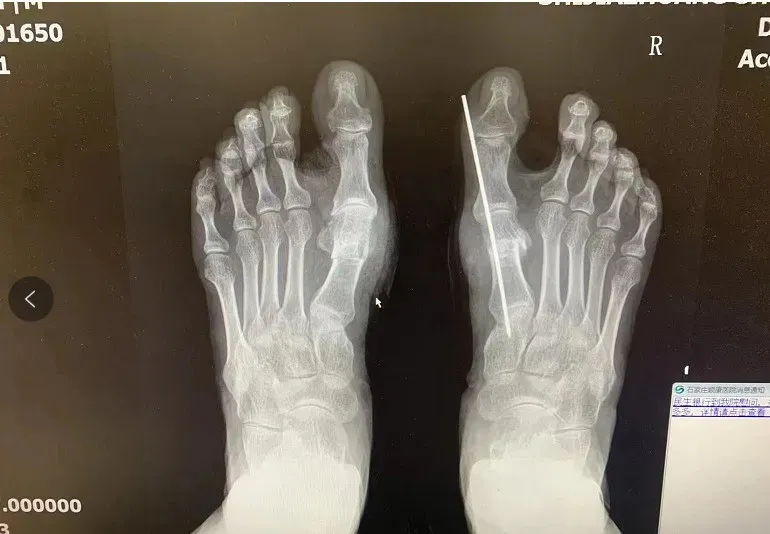

术前术后X光片对比图

术后X光片参考